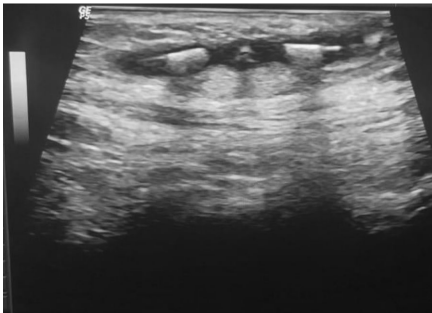

研究人员通过多模态影像学技术锁定了这个"逃亡者"的藏身之处。超声检查清晰显示出皮下混浊液性暗区中的IUD臂状结构(图2-3),同时盆腔X光片(图5)直观呈现了两个IUD的空间关系。最终通过精准的局部手术,这个引发慢性感染的"罪魁祸首"被成功取出(图6)。